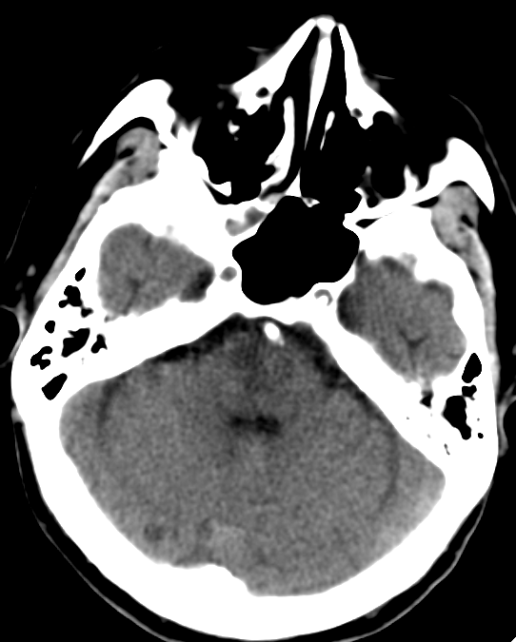

术后复查颅脑CT影像